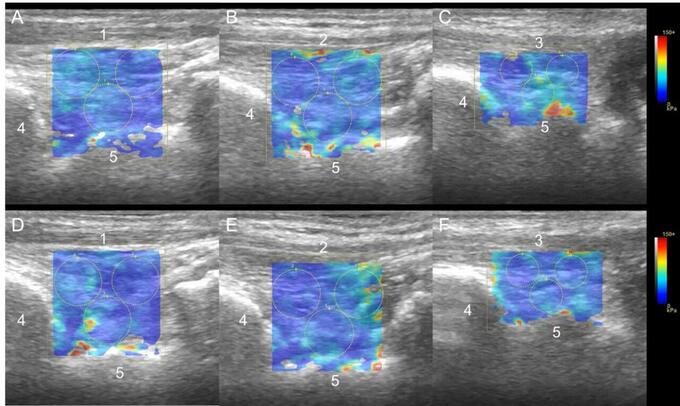

図 超音波画像(Shear wave elastography)

1:前脛骨筋腱、2:長母指屈筋腱、3:長趾伸筋腱、4:脛骨、5:距骨